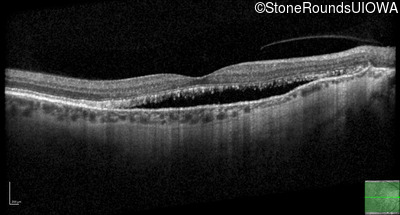

Age at visit: 58 years